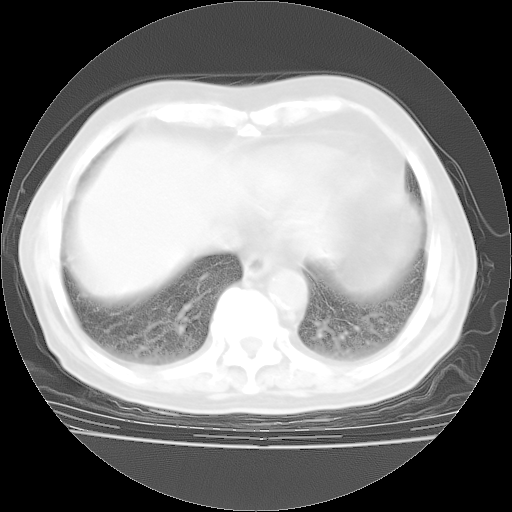

4月28日肺部CT——再次出现类似去年5月9日——透光度降低,“间质性”改变。

4月28日肺部CT——再次出现类似去年5月9日——磨玻璃样、间有“粟粒样”改变。